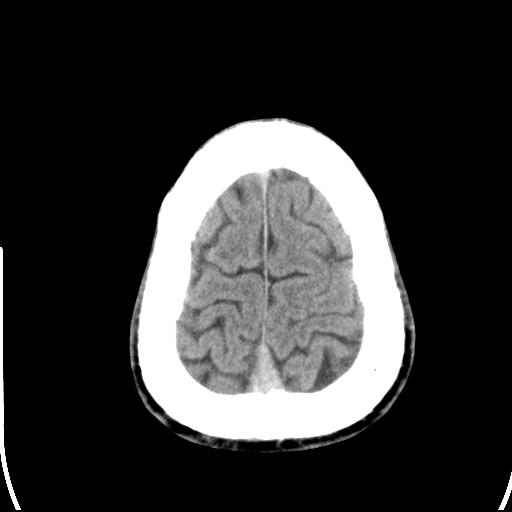

标题: CT25435:头皮下高密度影???

头皮下高密度结节影???临床上在老年男性比较常见。大家看看是什么?成因是? 本例患者,男性,51岁。外伤来诊。无染发史及发根植入史。

皮下钙化点

没见过,可能为毛囊钙化。

考虑钙化。